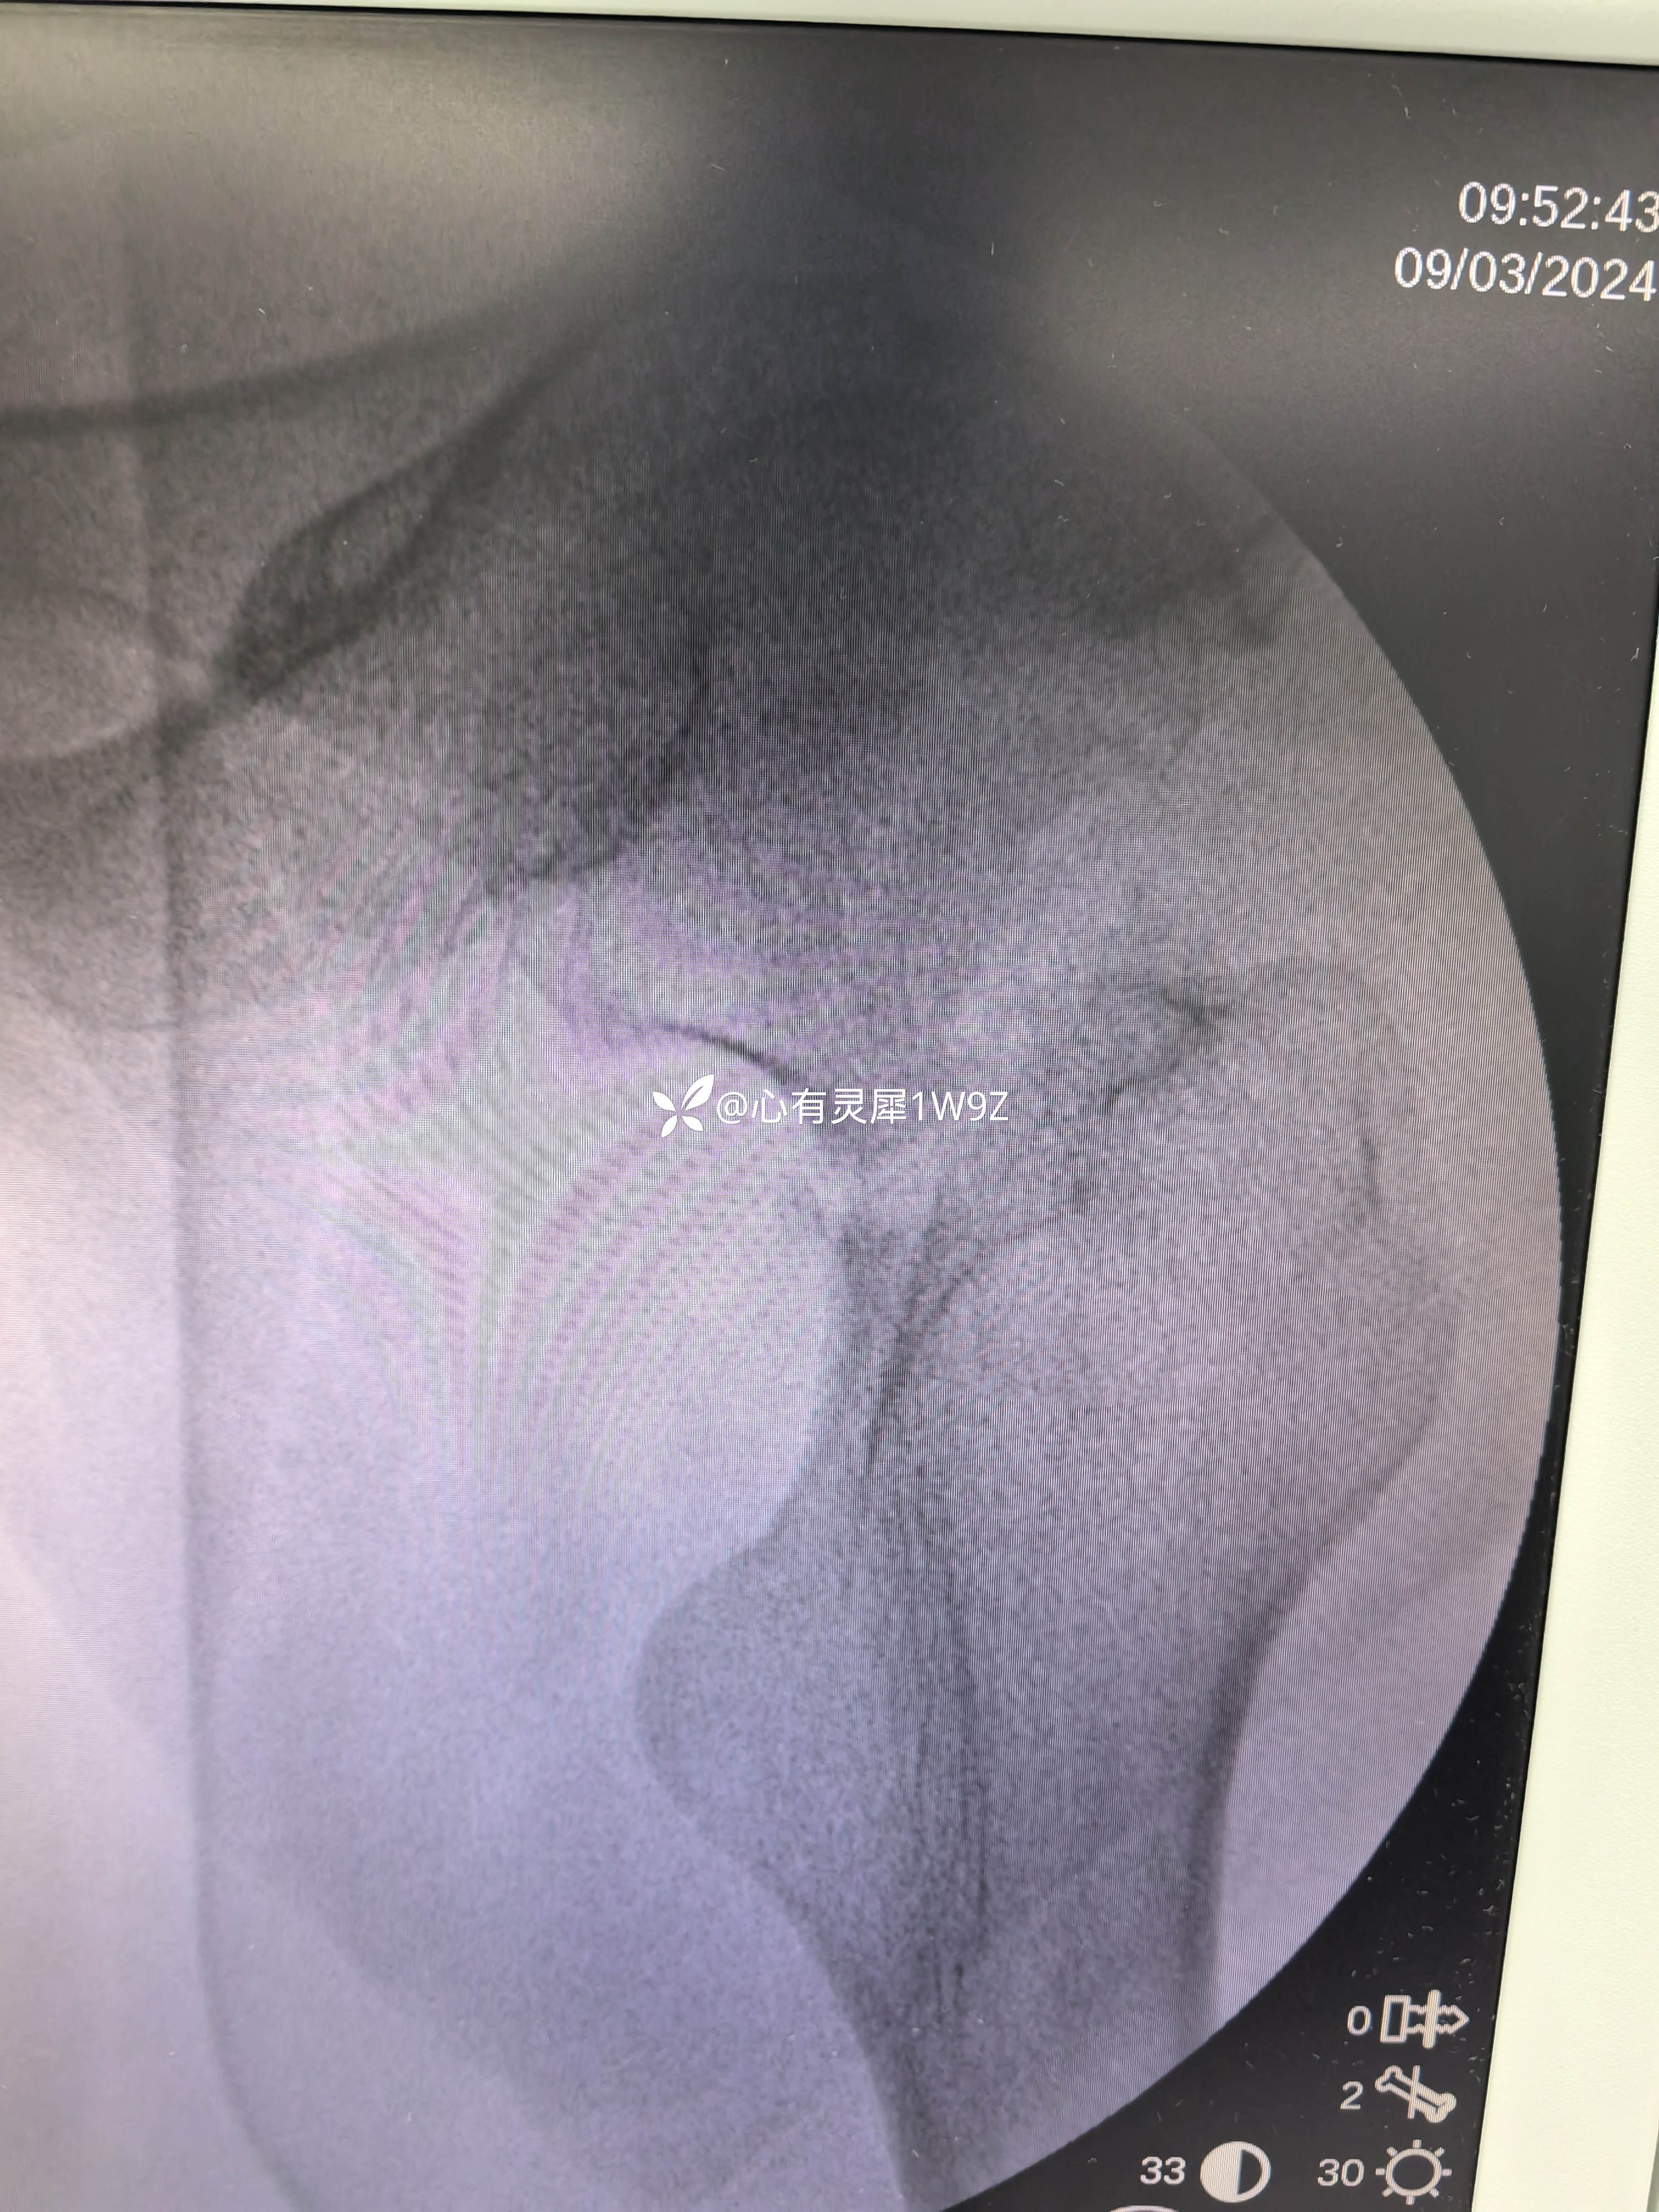

诊断:左侧股骨颈骨折(头下型)garden IV型

1,关于闭合复位的一些经验,该患者牵引床,先外旋外展牵引解锁后透视正位,根据情况再调整牵引内旋透视复位侧位。最后再内旋内收定位画线。